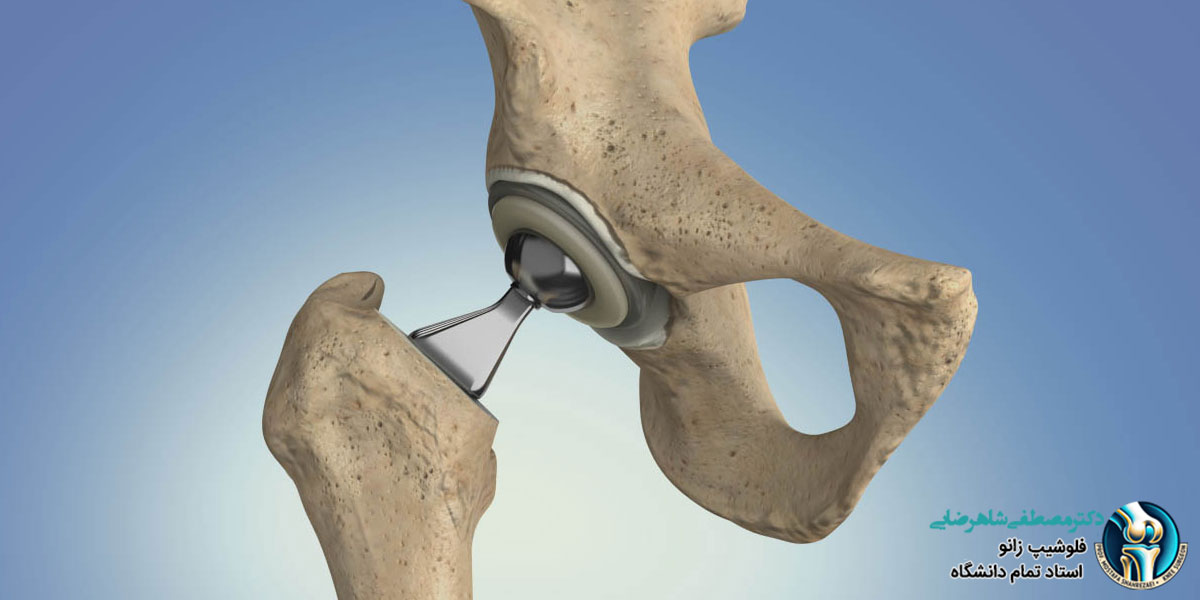

جراحی تعویض مفصل لگن می تواند به افرادی که دچار درد شدید و مشکلات حرکتی در این ناحیه هستند، کمک کند تا راحت تر و بدون درد حرکت کنند . بعد از جراحی، بدن نیاز به زمان دارد تا به مفصل جدید عادت کند. مدت زمان بهبودی برای هر فرد متفاوت است و به عواملی مثل سن، وضعیت سلامتی، مراقبت های بعد از جراحی و انجام تمرینات فیزیوتراپی بستگی دارد. بعضی از افراد بعد از چند هفته می توانند کارهای روزمره خود را انجام دهند، اما برای بعضی دیگر ممکن است ماه ها طول بکشد تا بتوانند دوباره به فعالیت های عادی برگردند.

بعد از جراحی تعویض مفصل لگن، بهبودی طی چند مرحله اتفاق می افتد و در هر مرحله رعایت نکات مراقبتی باعث بهتر شدن روند درمان می شود:

- روزهای اول بعد از جراحی: بیمار معمولا یک تا سه روز در بیمارستان می ماند تا پزشکان وضعیت او را بررسی کنند. در این مدت، برای کاهش درد، داروهای مسکن داده می شود. همچنین، فیزیوتراپیست تمرین های حرکتی ساده ای را آموزش می دهد تا مفصل خشک نشود و گردش خون در پاها بهتر شود.

- هفته های اول در خانه: بعد از ترخیص، بیمار باید در خانه استراحت کند، اما بی حرکت نباشد. برای راه رفتن، از عصا یا واکر استفاده می شود تا فشار زیادی به لگن وارد نشود. فیزیوتراپی و تمرینات مخصوص به قوی شدن عضلات کمک می کند. همچنین، بیمار نباید حرکاتی انجام دهد که باعث آسیب به مفصل جدید شود.

- ماه های بعدی: بعد از حدود شش تا دوازده هفته، بیمار می تواند بدون عصا یا واکر راه برود. در این مرحله، ادامه فیزیوتراپی برای افزایش قدرت و انعطاف پذیری مفصل خیلی مهم است. برخی بیماران می توانند فعالیت های روزمره را مجدد شروع کنند اما نباید فشار زیادی به مفصل بیاورند.

- بهبودی کامل: معمولا شش ماه تا یک سال طول می کشد تا بیمار کاملا درمان شوند. در این مدت، انجام تمرینات ورزشی سبک، رعایت توصیه های پزشک و خودداری از فعالیت های سنگین کمک می کند تا مفصل جدید سالم بماند و طول عمر بیشتری داشته باشد.